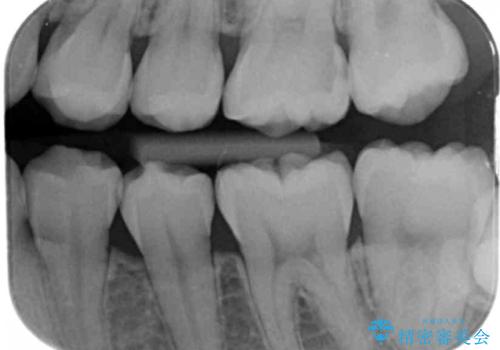

歯と歯の間に虫歯があったため適合の良いセラミックインレーで修復処置をしていきました。

歯と歯の間は虫歯の好発部位となっています。

適合の良いインレーでの修復により再発のリスクを下げることができます。